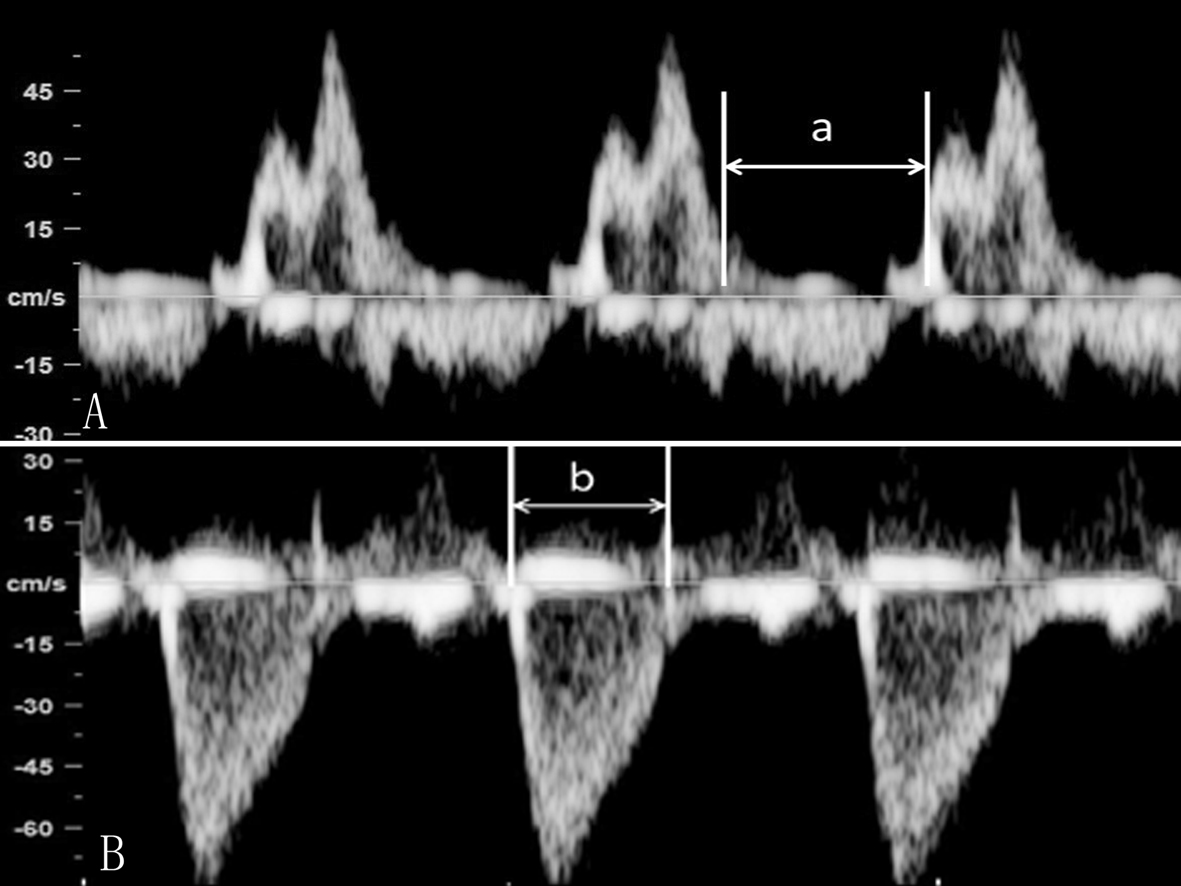

(1)MPI计算:①频谱多普勒检查心脏时,显示胎儿心脏五腔观,取样门放置在二尖瓣前叶远端和LV流出道结合部位,可以同时获得MVO血流和LV流出道血流,测量二尖瓣血流频谱前一心动周期A峰结束到下一心动周期E峰开始的时间间期,记为A,测量LV流出道血流时间为B,MPI = (A - B) / B;也有作者采取分别在MVO远端和AO瓣口获取血流频谱计算MPI的方法。②胎儿心脏TDI检查时测量显示Ea峰起点至Aa结束的时间(a)以及Sa持续时间(b),通过(a-b)/b获得MPI(图8、图9)。

图8 血流频谱法测量Tei指数

图9 改良的血流频谱法测量Tei指数

(2)注意事项:采用(a - b)/b的方法计算MPI简单方便,但不能区分等容收缩期和等容舒张期,二者还是有一定的不同的;在频谱多普勒检查采用不同的心动周期分别获取等容收缩期/等容舒张期和射血时间会由于心率的差异影响MPI计算的准确性。采取单一心动周期可以在一个屏幕上同时显示心室充盈及其射血时间可以避免心率对计算结果的影响。由于解剖结构的特点,该方法尤其适用于胎儿LV。在胎儿心脏四腔观上,采取3~4mm的取样门宽,多可以在同一幅图像上获得理想的LV流入道和流出道血流频谱,或还可获得RV流入道和流出道血流频谱;适当调节仪器增益条件和显示屏显示条件,准确、清晰地显示血流速度曲线或瓣环活动曲线可以准确地确定心脏活动时相,以确保MPI计算的准确性。